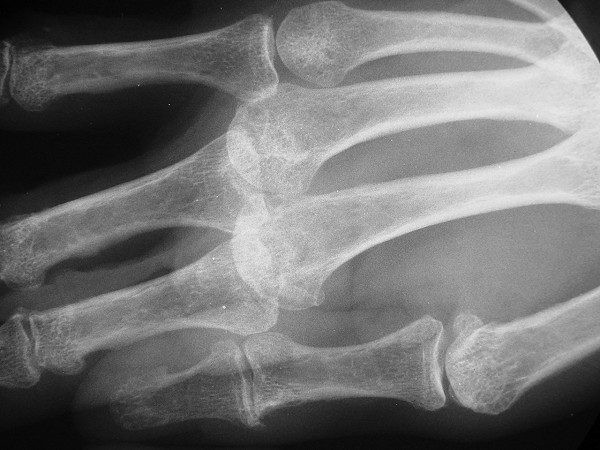

Lateral view of joint, showing chronic palmar subluxation -

Click for larger image

and after implant placement, subluxation corrected.